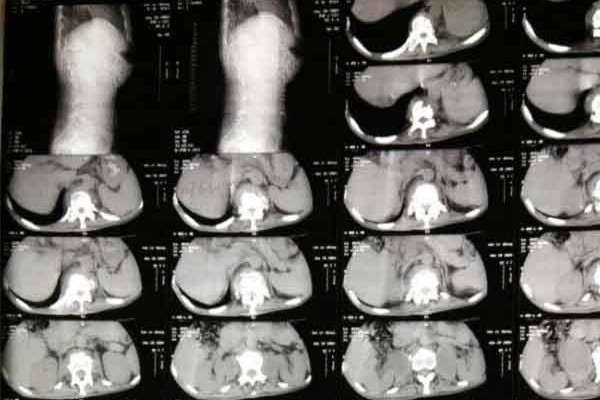

骨结核疾病发展较为缓慢,全身症状不太明显,较为隐蔽,好发脊柱、手、足、膝关节、肘关节等部位,骨结核疾病一旦发病,患者就会出现多种症状。

骨结核一般不具有传染性的,也就是说它无法通过呼吸道、消化道传播。但是,因为骨结核疾病成脓之后,就可能流窜至他处形成寒性脓肿,破溃后脓肿常伴有絮状痰样物,在这种情况下,因为脓液中含有结核菌,此时骨结核具有传染性。

骨结核患者常出现明显全身症状,如发热、寒战、咳嗽,同时会伴有胸膜疼痛、体重减轻和乏力等,急性发展的情况下会并发肺部的感染,这时就可能转发为肺结核,而肺结核是具有传染性的,这时女性患者就不要怀孕生孩子。否则,不但耽误病情,还会让孩子具有感染的风险。